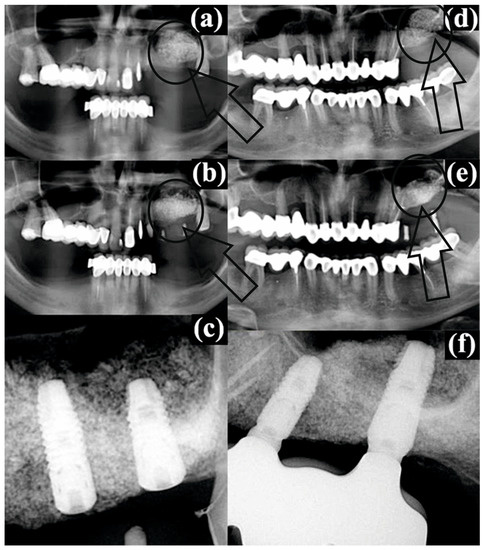

As was mentioned in the previous section, for all patients as a standard procedure a CBCT evaluation was performed (before surgery, post operatory and after the healing period/with dental implants). The results are presented in Figure 2.

For patient #2, the augmented bone material in the left sinus immediately after sinus floor augmentation (Figure 2a) can be clearly observed as a spongy aerated filling compared with the compact structure from the rest of periodontium. After four months of healing, the conformation was the same, but with a small advance of the filling to the left side and sticking to the sinus floor wall (Figure 2b, pointed by a small arrow) with the same gray shades very similar to the image of a lattice. Regarding patient #3, the same conformation can be noticed after the sinus floor augmentation (Figure 2d) as for patient #2. However, after the healing period, for the radiographic image (Figure 2e) a “white spot” can be observed as a compact area of bone substitute (pointed by a small arrow) with no lattice structure.

Values presented in Table 5 for RH represent the confirmation (above all) for the evaluation and confirm results/conclusions from the Raman expertise. Comparing the obtained results with the radiographic images from the CBCT for patients #2 and #3, we conclude that those methods are more accurate in bone quality evaluation. We emphasize that for patients #1, #2, #4 it was a successful augmentation, and for patients #3 and #5 it was just “partial”. Using just the primary evaluation with the CBCT, all patients were considered recovered and healed from the medical point of view.

Figure 2. Radiographic images of patient #2: (a) the augmented bone in the left sinus immediately after sinus floor augmentation-highlighted with arrow and circle, (b) postoperative conditions after 4 months of healing-highlighted with arrow and circle, (c) dental implants in the augmented bone at 7 months after augmentation; and patient #3: (d) the augmented bone in the left sinus immediately after sinus floor augmentation-highlighted with arrow and circle, (e) postoperative conditions after 4 months of healing-highlighted with arrow and circle, (f) dental implants in the augmented bone at 7 months after augmentation. The augmentation loci are encircled and arrow are pointing to the regions of interest.